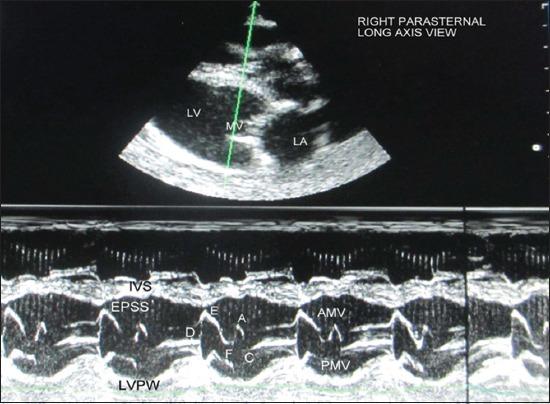

A total of 18, clinically healthy, adult Pantja goats of either sex, aged 2-4 years and weighing 10-44 kg were included in the study. Echocardiographic examination was performed in the standing unsedated animal. All measurements were made from the right parasternal long-axis left ventricular outflow tract view of the heart. The following parameters were recorded: Left ventricular internal diameter at diastole and systole, interventricular septal thickness at diastole and systole, left ventricular posterior wall (LVPW) thickness at diastole and systole, end diastolic and systolic volumes, stroke volume, fractional shortening, ejection fraction, percent systolic thickening of interventricular septum, percent systolic thickening of LVPW, cardiac output, left atrial (LA) diameter at diastole and systole, aortic (AO) root diameter at diastole and systole, LA/AO, LA posterior wall thickness at diastole and systole, left ventricular ejection time, DE amplitude, EF slope, AC interval and e-point to septal separation.

本研究共纳入18只2至4岁、体重10至44千克、临床健康的成年潘贾山羊,雌雄不限。在未使用镇静剂的站立动物身上进行超声心动图检查。所有测量均从心脏右胸骨旁长轴左心室流出道视图进行。记录以下参数:舒张末期和收缩末期左心室内径、舒张末期和收缩末期室间隔厚度、舒张末期和收缩末期左心室后壁(LVPW)厚度、舒张末期和收缩末期容积、每搏输出量、缩短分数、射血分数、室间隔收缩期增厚百分比、LVPW收缩期增厚百分比、心输出量、舒张末期和收缩末期左心房(LA)直径、舒张末期和收缩末期主动脉(AO)根部直径、LA/AO、舒张末期和收缩末期LA后壁厚度、左心室射血时间、DE幅度、EF斜率、AC间期以及e点至室间隔距离。